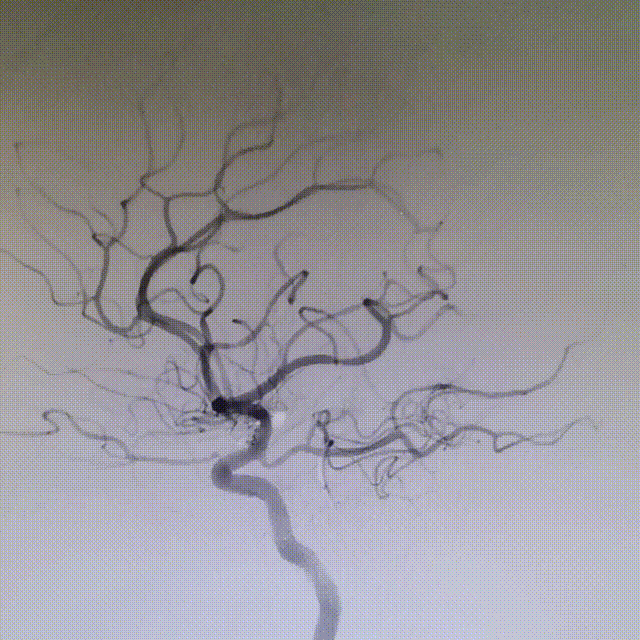

XT-17微导管依次填入Target 5-15/4-8/2-6/2-6/1.5-3,造影确认填塞效果基本满意。

术后即刻工作位造影显示,支架全程打开形态良好,充分贴壁。

术后即刻正/侧位造影显示:各分支血管血流通畅,无出血情况,瘤体内无造影剂充盈。